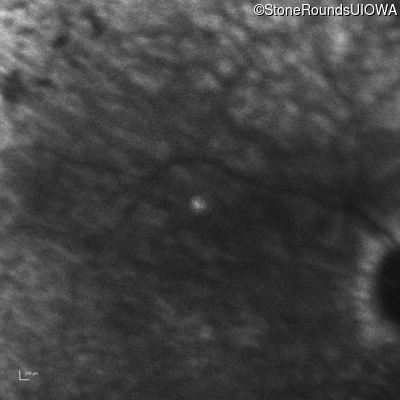

Infrared Fundus Photograph - Right - Hand Motion sc

Exemplar